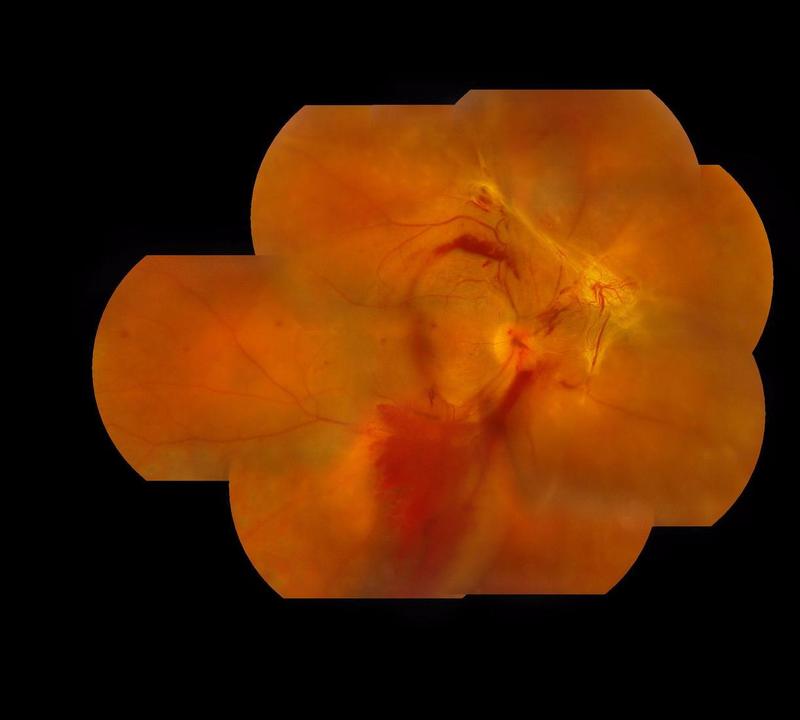

眼科日記:血壓高導(dǎo)致的眼內(nèi)出血(玻璃體積血)

今天收了個(gè)雙眼玻璃體積血要做玻璃體切除手術(shù)的患者,追問病史,患者有一天頭暈,迷糊,血壓高,然后雙眼都視力下降,看不清了。一查眼B超,眼球里面大量的血,考慮血壓高導(dǎo)致的眼球內(nèi)出血。在此提醒,如果有高血壓的患者,一定要系統(tǒng)用藥,控制好血壓,避免血壓波動(dòng)

“玻璃體出血”是怎么回事?玻璃體出血就是玻璃體積血,一般是由各種眼底病變(例如糖尿病視網(wǎng)膜病變、視網(wǎng)膜靜脈阻塞、滲出性老年性黃斑變性、視網(wǎng)膜裂孔、外傷等)導(dǎo)致血管破裂,血液進(jìn)入玻璃體導(dǎo)致造成視力下降。(圖1) 圖1.增殖性糖尿病視網(wǎng)膜病變導(dǎo)致的玻璃體出血。 “玻璃體出血”有什么癥狀呢?癥狀取決于玻璃體出血的多少和部位。少量出血時(shí)可能沒有任何癥狀,或感覺有眼前的黑影,類似“飛蚊癥”;出血量較多時(shí),患者感覺眼前暗影飄動(dòng),或似有紅玻璃片遮擋,反復(fù)出血的患者感覺像眼前“冒煙”,視力明顯下降。 得了“玻璃體出血”怎么辦?患者應(yīng)盡快到眼科門診就診,如果出血量較少,B超檢查排除視網(wǎng)膜脫離、視網(wǎng)膜裂孔及腫瘤等原因后,可以先觀察,口服促進(jìn)出血吸收的藥物,大概1個(gè)月出血吸收后,再次散瞳檢查眼底,明確出血原因,決定下一步治療方案。 如果出血合并視網(wǎng)膜脫離、裂孔等,或觀察1月后出血沒有明顯吸收,則應(yīng)考慮手術(shù)治療明確病因,同時(shí)治療眼底病變。 特別要注意的是糖尿病患者,一旦出現(xiàn)了玻璃體出血,一定不要等,當(dāng)糖尿病視網(wǎng)膜病變進(jìn)展到增殖期時(shí),會(huì)出現(xiàn)視網(wǎng)膜新生血管,這種異常血管非常容易破裂出血,導(dǎo)致玻璃體出血。一開始可能出血量較少,且很快就吸收了,患者往往用藥或觀察就能好轉(zhuǎn),因此沒有引起足夠的重視;但隨著病變的進(jìn)展,出血會(huì)越來越頻繁,出血量也會(huì)逐漸增多,如果不能針對(duì)病因(就是新生血管)進(jìn)行治療,不僅會(huì)影響視力,還有可能進(jìn)展為牽拉性視網(wǎng)膜脫離,到那時(shí)再治療即使手術(shù)做的再漂亮,視力也往往不能恢復(fù)。因此,對(duì)于糖尿病患者,一旦出現(xiàn)眼前黑影、視物模糊等癥狀時(shí),應(yīng)及時(shí)到眼科門診就診,檢查眼底是否發(fā)展到了增殖期,這時(shí)應(yīng)及時(shí)的進(jìn)行視網(wǎng)膜激光治療,可以有效的抑制病變的進(jìn)展,避免反復(fù)出血和視網(wǎng)膜脫離導(dǎo)致的不可逆性視力喪失。 “玻璃體出血”是怎么治療的?1) 藥物治療:出血量較少,B超檢查排除視網(wǎng)膜脫離、視網(wǎng)膜裂孔及腫瘤等原因后,可以口服促進(jìn)出血吸收的藥物。 2) 手術(shù)治療:手術(shù)可以治療不能自行吸收的玻璃體出血、合并視網(wǎng)膜脫離等玻璃體出血等。這種手術(shù)就是玻璃體切割手術(shù)(簡(jiǎn)稱玻切手術(shù)),是一種微創(chuàng)手術(shù),通過3個(gè)不到1mm的小針孔進(jìn)行手術(shù)(圖2、3),直視下進(jìn)行玻璃體切割清除玻璃體出血、明確出血原因,同時(shí)聯(lián)合視網(wǎng)膜激光、電凝、眼內(nèi)惰性氣體或硅油填充等操作治療出血病因。 圖2 玻璃體切割術(shù)。 圖3.玻璃體切割術(shù)三個(gè)微創(chuàng)切口。